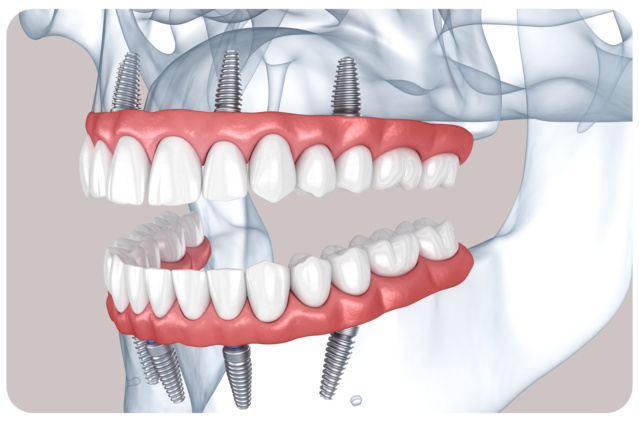

SOLUTION 01

자연치의 저작력과 심미를 되찾는

전체임플란트

다양한 요인으로 인해 치아를 다수 상실하였거나

모두 상실하여 제 기능을 수행할 수 없는 경우

전반적인 범위에 임플란트를 수복하여

자연치아의 기능과 심미를 대체할 수 있는 치료법입니다.

구강 상태에 따라 6 - 10개 정도의 고정체를 식립한 후

연결된 형태의 인공치아를 제작하여 장착합니다.